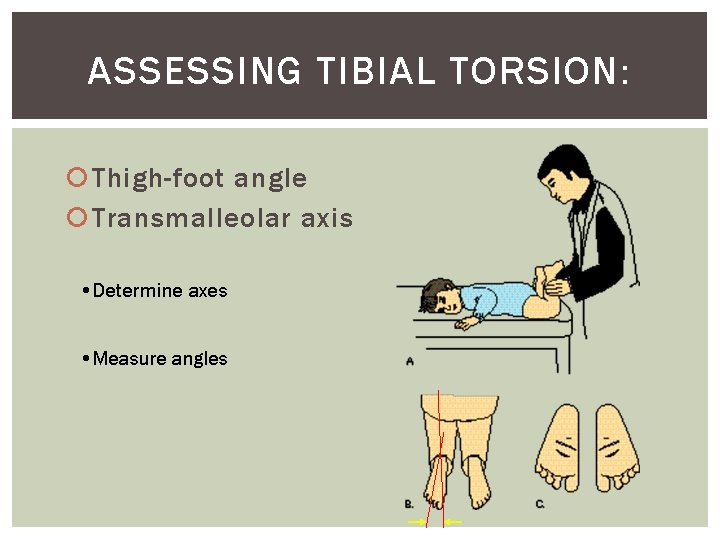

ASSESSING TIBIAL TORSION: Thigh-foot angle Transmalleolar axis • Determine axes • Measure angles